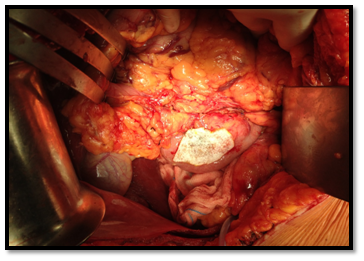

In September of 2014, she underwent a tumour enucleation, without complications (Figure 4). In the postoperative period the patient resolved symptoms and hypoglycaemia did not recur. The histopathological study confirmed a low-grade neuroendocrine tumour with high reactivity to a-chromogranin and synaptophysin (Figure 5A-D). Seven months post-surgery she didn’t present hyperglycaemia or diabetes mellitus.

• Figure 4 Surgery. Tumor enucleation.